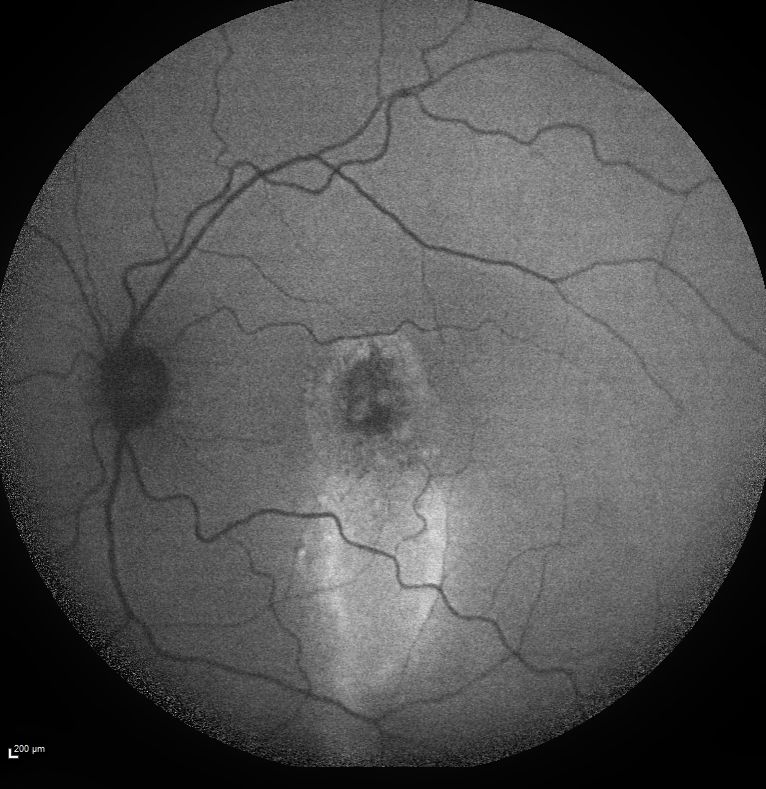

✚ Autofluorescence

Mise en évidence d’une coulée gravitationnelle typique, traduisant l’évolution chronique de la maladie et les altérations de l’épithélium pigmentaire.